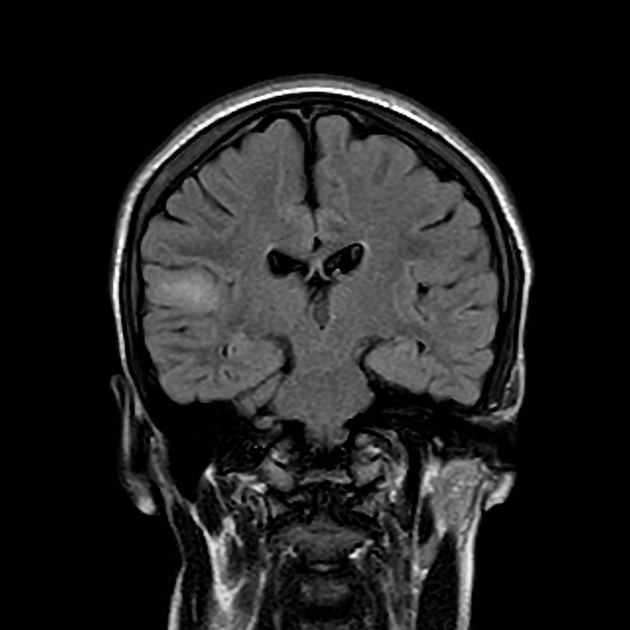

Focal cortical dysplasia is another cause of seizures, esp if it occurs in the frontotemporal lobes. What are some general features of FCD?

Blumcke classification of focal cortical dysplasia (2011). Types 1 to 3

cortical thickening

blurring of white matter-grey matter junction with abnormal architecture of subcortical layer

T2/FLAIR signal hyperintensity of white matter with or without the transmantle sign

T2/FLAIR signal hyperintensity of grey matter

abnormal sulcal or gyral pattern

segmental and/or lobar hypoplasia/atrophy

there is no oedema, calcification, or contrast enhancement